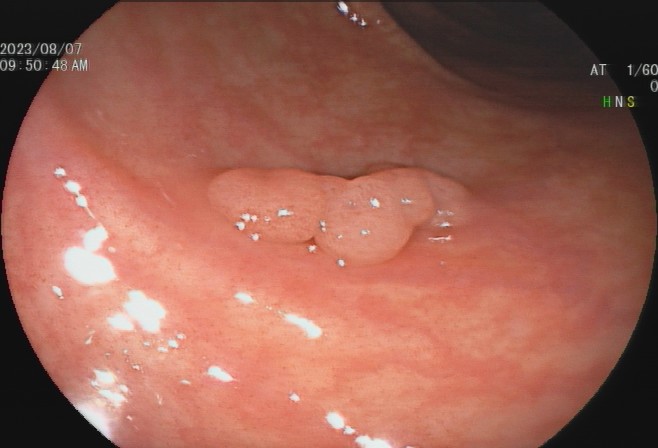

肠息肉是指突出于肠腔表面的隆起,在没有确定病理性质前统称为息肉,其发生率通常随年龄增加逐渐上升,病变部位以结直肠多发,与结直肠癌的发病有密切关系。

少数患者会发生便血,而结肠息肉很多的患者也可能会发生腹泻、黏液便、腹痛等症状,但这些症状无特异性,因此要确诊结肠息肉主要依赖结肠镜等检查,多数患者是在体检或因其他疾病做结肠镜时才被发现。

95%以上的结肠癌是从结肠息肉一步步转变而来,因此,结肠息肉一旦发现应该及时切除。发现息肉和早期肠癌,在内镜下就可以把这颗“定时炸弹”切除,创伤也小,对预期寿命几乎没有影响。